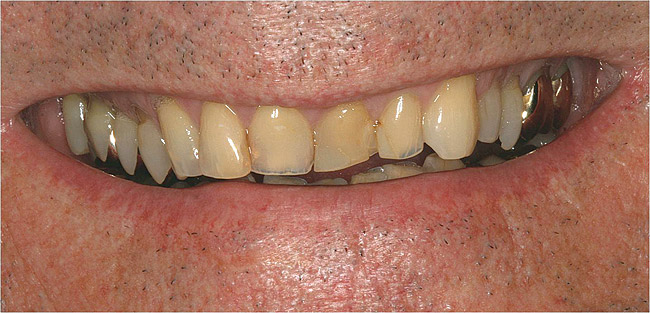

Figure  5  Loss of tooth surface and yellowing of teeth in a young patient with untreated GERD.

Figure 5

The effects of tooth surface loss vary depending on the severity of the tooth tissue loss. These effects include loss of thickness of enamel and exposure of the underlying dentin, translucency, and yellowing. Also, the occlusal surfaces may display wear facets, or the cusps may flatten.

Characteristics of damage to tooth structures caused by acidity include wear on the occlusal surfaces of molars and a saucer shape on the cusps of molars (perimolysis).12 The erosion can vary from minor and subtle changes on the tooth surface, ie, loss of luster, a dull or matted look, to cupping on occlusal surfaces or incisal edges, which may extend to dentin. Usually, the erosive lesions demonstrate greater width than depth. When combined with abrasive forces or stresses, the tooth surface loss may occur at a faster rate (Figure 2, Figure 3, Figure 4 and Figure 5).